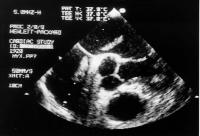

Pseudomyxom in beiden Atrien

Figure 1: Transesophageal echocardiography: Pseudomyxoma in the right and left atrium